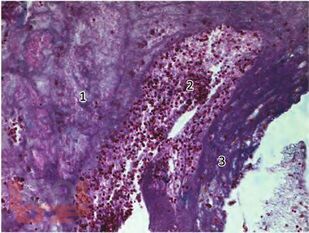

В монографии представлены результаты многолетнего опыта работы по изучению этиологии, патогенеза и исходов одонтогенных верхнечелюстных синуситов в повседневной практике врачей-оториноларингологов и стоматологов. Представлены уникальные данные о причинах и условиях возникновения синуситов, механизмах развития, течения и исходах, а также результатов морфологических исследований в зависимости от характера этиологических факторов и факторов риска. Представлены инновационные методы диагностики и лечения синуситов, обеспечивающие персонализированный подход в прогнозировании исхода заболевания.